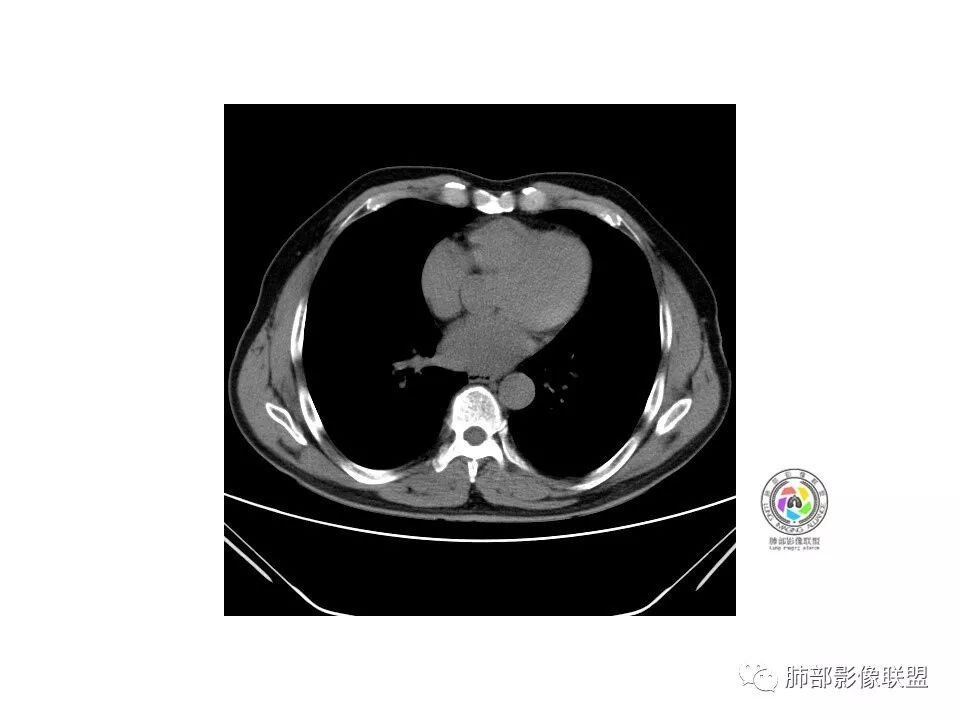

1.纵膈窗未显示;水平裂有轻微凹陷,那个条索影,有形成机理进一步分析;前方那个血管,可能是肺动脉?有一定弯曲度(向病灶),后方这个是肺静脉;3个小叶凹,有可能,受到阻挡,邻近小血管有相应改变;薄层那个细小血管有弯曲,形成部分实性;

2.大小:估计15*10mm左右;

3.CT值:混杂,有些偏高;

4.周围小血管,有形成毛刺趋势;

5.血管:如上述;

6.胸膜和叶间裂:有轻微牵拉;

诊断:浸润性腺癌;鉴别:炎性结节;